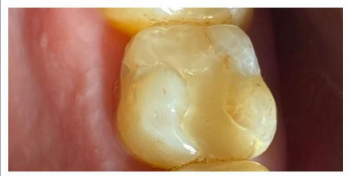

Равиля Равилевна: «Ваша улыбка – показатель здоровья и благополучия. Не даром говорят глаза – зеркало души, а зубы – зеркало здоровья. Цель моей работы – здоровые и красивые зубы пациента. А лучшая награда, когда пациент и окружающие его люди не могут отличить леченый мною зуб от родного здорового!»